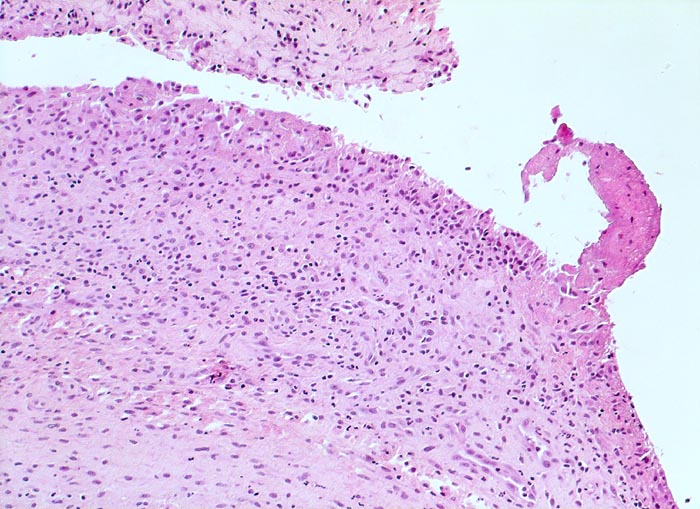

In Abhängigkeit von der Entzündungsdauer werden unterschiedliche morphologische Befunde beschrieben. Die initiale proliferative Phase ist charakterisiert durch eine Hyperplasie der Synovialis, Fibrinexsudate und Gelenkergüsse. In der destruktiven Phase kommt es zur Zerstörung von Gelenkknorpel und gelenknahem Knochen durch Ausbildung eines intraartikulären Pannusgewebes (> 194). Die ausgebrannte Phase ist gekennzeichnet durch eine synoviale Fibrose mit zunehmender Ankylose (= Gelenkversteifung).

Typische histologische Veränderungen sind eine synoviale Zottenhyperplasie, Verbreiterung der Deckzellschicht unter Einschluss mehrkerniger Riesenzellen, Fibrinexsudate und synoviale Ulzerationen, Infiltrate von Lymphozyten teils in Form von Lymphfollikeln, Plasmazellen, neutrophilen Granulozyten, Makrophagen und Siderophagen, sowie Einschlüsse von Knorpel- und Knochenfragmenten (Detritussynovialitis). Die histologischen Befunde der Synovialis korrelieren oft nicht mit den klinischen Angaben. Trotz fortgeschrittener Gelenkdestruktion mit ausgeprägter klinischer Symptomatik können Synovialektomiepräparate nur sehr geringe pathologische Veränderungen zeigen. Oft ist auch nicht mehr zu eruieren, welche Läsionen Folge der Grundkrankheit und welche Folge diverser intraartikulärer Therapien oder begleitender Superinfektionen sind.

Bei einem grösseren Teil der Gelenkerkrankungen ist die histopathologische Diagnostik dadurch eingeschränkt, dass nur uncharakteristische Befunde zu erheben sind. Um die Synovialitisdiagnostik zu standardisieren, wurde ein Gradierungssystem, der sog. Synovialitis-Score, vorgeschlagen. Gradiert werden die Dicke der Deckzellschicht, die Zelldichte des synovialen Stromas und das chronische Entzündungsinfiltrat. (0-1 Punkt: keine Synovialitis; 2-4 Punkte: low-grade Synovialitis; 5-9 Punkte: high-grade Synovialitis). Der Befund einer hochgradigen Synovialitis als diagnostisches Kriterium für eine rheumatische Erkrankung besitzt eine Sensitivität von 60.5% und eine Spezifität von 95.5%. Die diagnostische Synovialisbiopsie bleibt aber ausgewählten und klinisch unklaren Konstellationen vorbehalten und ist in der Mehrzahl der Fälle nicht erforderlich.

• Synovialis mit verplumpten Zotten.

• Stark proliferierte mehrreihige synoviale Deckzellschicht.

• Hyperzelluläres Stroma mit lymphoplasmazellulärem Entzündungsinfiltrat mit Ausbildung von Lymphfollikeln.